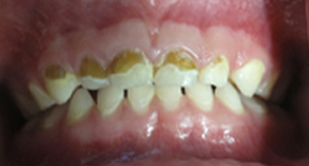

Fluoride is a naturally occurring element, which has shown to prevent tooth decay by as much as 50-70%, Despite the advantages, too little or too much fluoride can be detrimental to the teeth. With little or no fluoride, the teeth aren’t strengthened to help them resist cavities. Excessive fluoride ingestion by young children can lead to dental fluorosis, which is typically a chalky white discoloration (brown in advanced cases) of the permanent teeth. Be sure to follow your pediatric dentist’s instructions on suggested fluoride use and possible supplements, if needed.